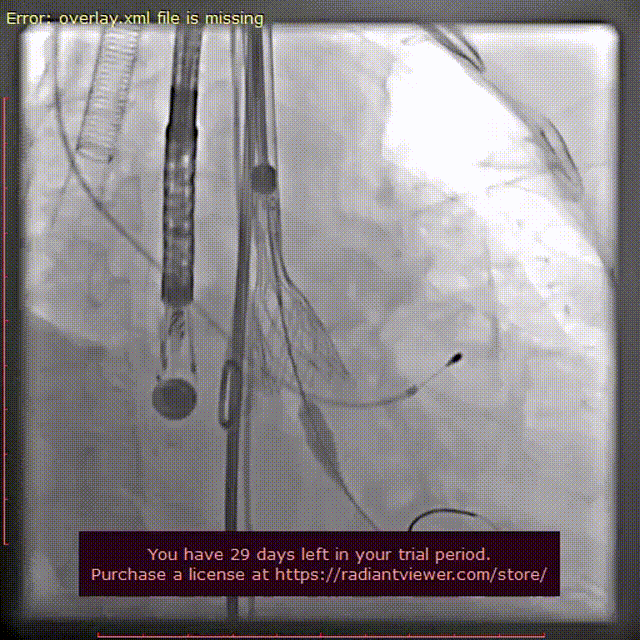

TaurusElite输送系统顺利过弓跨瓣后,AV26瓣膜瓣环上4mm定位释放,到工作位后造影显示位置良好,但受钙化影响有中量瓣周漏。随后进行回收,瓣环上6mm再次定位释放。

瓣膜初次释放至工作位

瓣膜再次释放至工作位